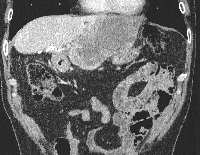

Πρόκειται για άνδρα ασθενή 45 ετών ο οποίος πριν από ένα χρόνο υποβλήθηκε σε κεντρική ηπατεκτομή για αδενοκαρκίνωμα αγνώστου πρωτοπαθούς εστίας. Έξι μήνες μετά την αρχική ηπατεκτομή και αφού είχε ολοκληρώσει τη μετεγχειρητική χημειοθεραπεία, διαπιστώθηκε ότι έφερε νέα μάζα στο 2ο και 3ο ηπατικό τμήμα (εικόνα 1), μακριά από το σημείο της πρώτης επέμβασης. Για άλλη μία φορά ο εκτεταμμένος έλεγχος (ενδοσκοπήσεις, αξονικές και μαγνητικές τομογραφίες, PET-CT scan) δεν ανέδειξε πρωτοπαθή εστία. Υποβλήθηκε σε έξι νέους κύκλους προεγχειρητικής χημειοθεραπείας (neoadjuvant) που οδήγησαν σε μερική ανταπόκριση. Πέντε εβδομάδες μετά τον τελευταίο χημειοθεραπευτικό κύκλο υποβλήθηκε σε αριστερή πλάγια επανηπατεκτομή (redo hepatectomy). Η μάζα αφαιρέθηκε in toto, σε υγιή όρια ηπατικού παρεγχύματος (εικόνα 2) αλλά με περιθώριο εκτομής μικρότερο του ενός cm. Για το λόγο αυτό εφαρμόστηκε εστιακή παρεγχυματική καταστροφή της επιφάνειας διατομής με μικροκύματα (εικόνα 3). Το εγχειρητικό πεδίο μετά την απομάκρυνση του παρασκευάσματος φαίνεται στην εικόνα 4. Την 5η μετεγχειρητική ημέρα πραγματοποιήθηκε αξονική τομογραφία που δεν ανέδειξε παθολογικά ευρήματα (εικόνα 5). Ο ασθενής έλαβε εξιτήριο την 6η μετεγχειρητική ημέρα.